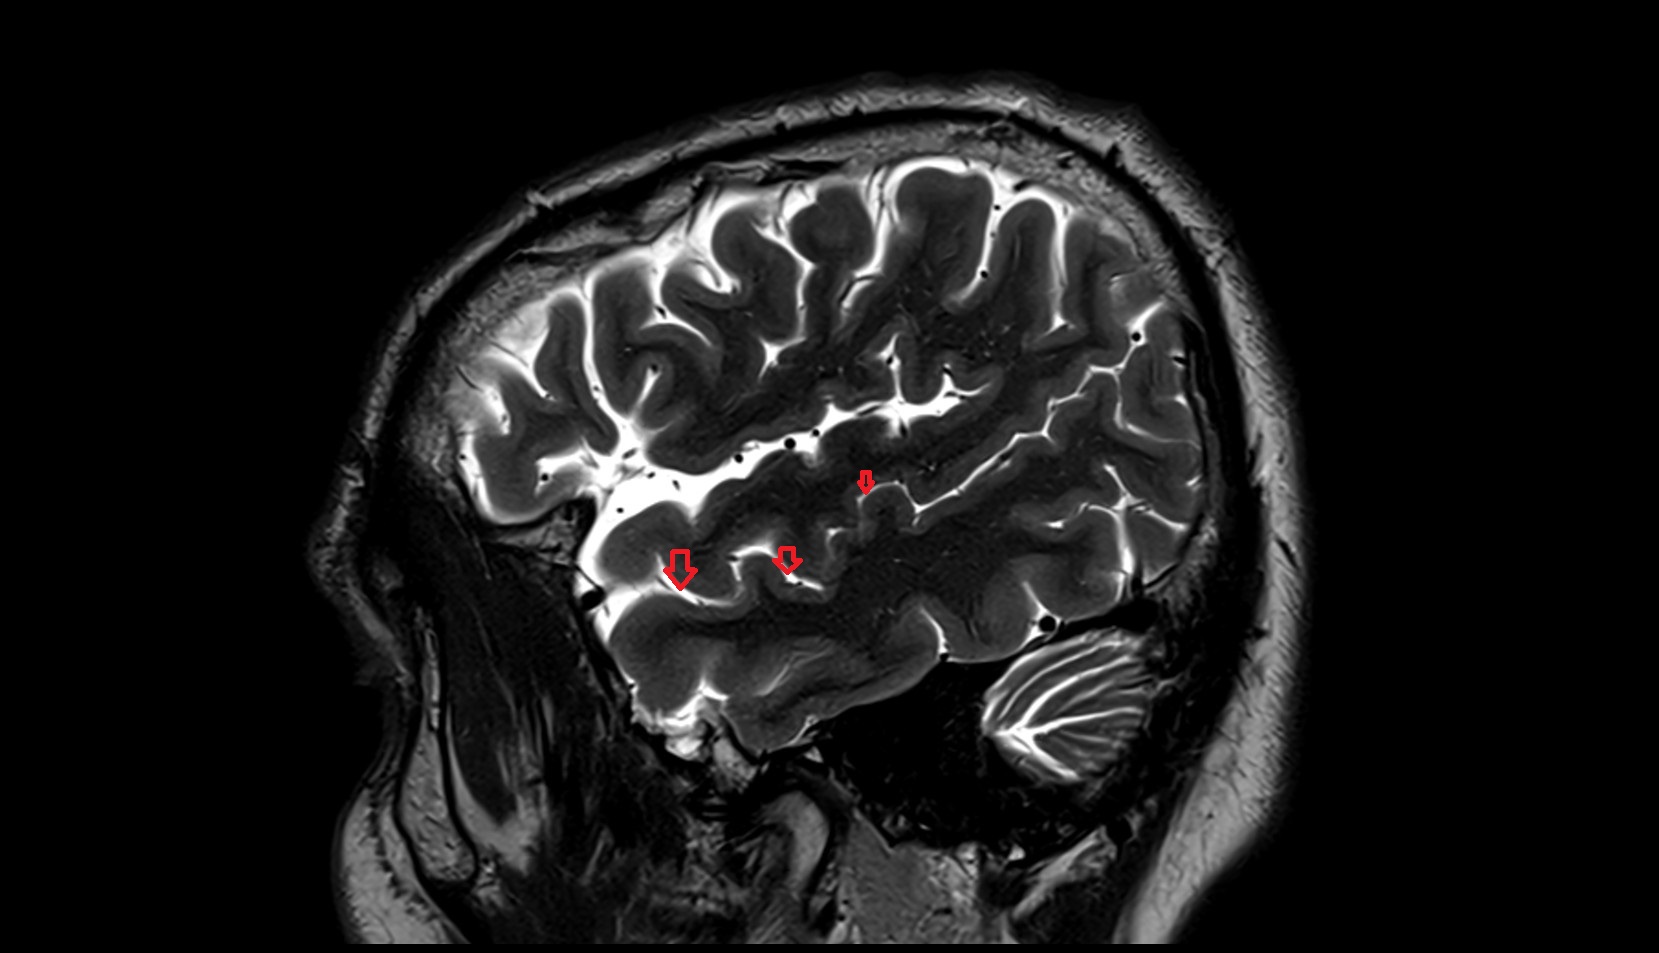

- Central sulcus

- Parietooccipital sulcus